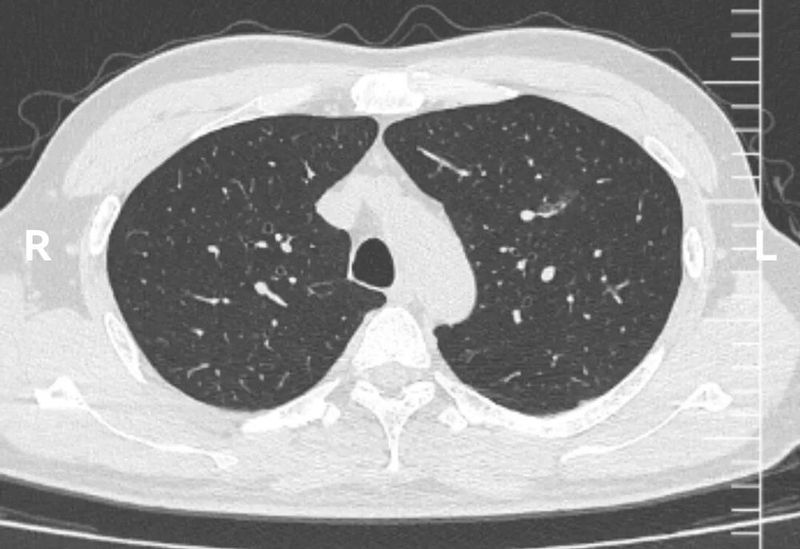

CT图像

这个左上肺混杂磨玻璃结节CT图像非常有特点,首先,磨玻璃成分为主,而且磨玻璃成分边界模糊不清。这本身就是炎症的典型表现。其次,实性成分的形态边界比较清楚,没有分叶、血管异常等形态。